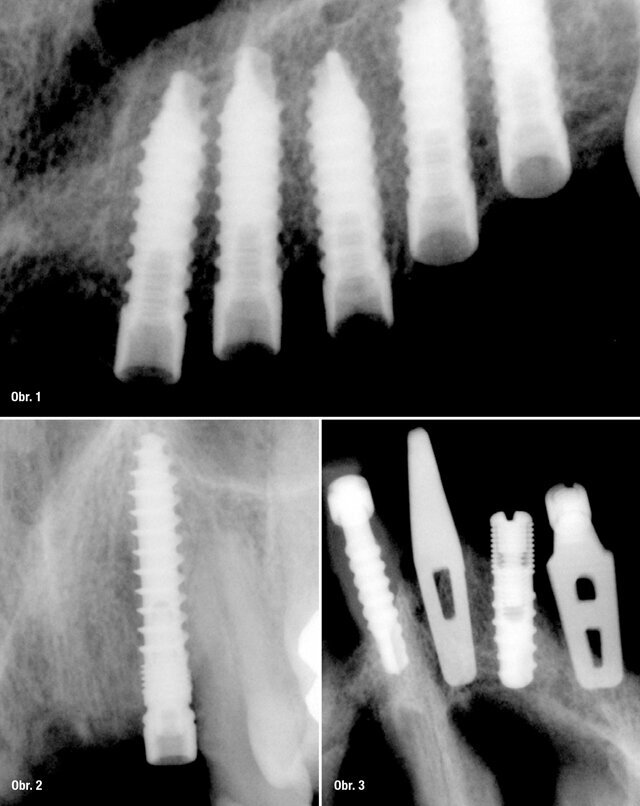

UIS IMPLADENTA obsahuje kompletní nabídku jednofázových a dvoufázových implantátů. Mini samořezné (MS), bikortikální samořezné (BS)

– jednofázové implantáty. V nabídce současně dvoufázové úzké válcové (NS) a cylindrické samořezné implantáty (CS) včetně abutmentů. Celistvost a kompletnost zajištuje speciální nabídka čepelkových – plátkových implantátů řada PROFI+.

ŘADA PROFI+ je určena pro zkušené implantology. Z poznatků uživatelů je patrné, že plátkové – lístkové jednofázové implantáty B1 a B2 jsou považovány za 100% spolehlivé.

Při správné indikaci jsou vhodné jako pilíře k provedení pevné (někdy i hybridní) protetické práce. Jejich tvar má výhodu v tom, že orální část implantátu přechází do ramének nitrokostní části pozvolně se rozšiřujícím pilířem, čímž na přechodu mezi orální a nitrokostní částí nejsou žádná podsekřivá místa ani ostré hrany.

Sériová výroba nejčastěji používaných plátkových implantátů nabízí více než 50 druhů tvarů implantátů a umožňuje jejich velmi široké klinické využití.

Implantát řady PROFI+ má 6mm matné, zdrsněné části, následuje 5mm lesklý povrch s bodem pro určení, kam musí zasahovat implantát do kostní tkáně. Nitrokostní část je matná a zdrsněna pískováním s otvory pro zvýšení sekundární stability.

B1 – jednofázové plátkové implantáty jsou určeny do místa, kde je výška a síla kosti omezena čelistními dutinami a nervovými kanály. Jsou vhodné k okamžitému zatížení. Tento typ implantátů se dá s pomocí ohýbacích kleští upravit do osy. Toto ohýbání se však musí provést mimo alveol a až takto upravený implantát se pomocí zatloukače usadí do kostní tkáně. Následuje sutura mukoperiostu.

B2 – dvoufázové plátkové implantáty, mají podobné využití jako implantáty typu B1, ale i pro přímou aplikaci do plošných extrakčních ran se zakotvením do neporušené části alveolu.

Ke speciálnímu typu implantátů UIS IMPLADENTA se řadí samořezné bikortikální implantáty (BS) – jednofázové implantáty určené k okamžitému zatížení. Jsou vhodné zejména do bradové oblasti dolní čelisti. Méně vhodné do oblasti horních čelistí. Zavádět lze jak do vhojené alveolární kosti, tak i okamžitě po extrakcích frontálních zubů, pokud je dostatečně široký a vysoký kostní alveol nebo tělo dolní čelisti. V současnosti

se vyrábějí v nejčastějších délkách 12/14/16/18/20 a 22 mm, z čehož orální část má výšku 5,5 mm. Průměr implantátu je 3,5 mm.